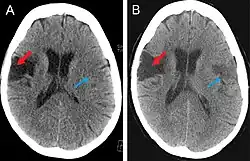

(A) CT scan of a patient with middle cerebral artery stroke illustrating hypodensity areas within the temporal and frontal lobes. (B) CT scan displaying an ischemic stroke bordering the fronto-parietal opercular cortex (red arrow) and a left-sided ichemic lesion of the fronto-parietal opercular cortex (blue arrow).

CT scan

This computer-tomography type of imaging is one of the most used in any clinical environment and although it can detect some of the brain areas affected by a stroke or a trauma it does not provide the same acuity as the magnetic resonance imaging. CT scans can also reveal, in patients with the syndrome, the bilateral cortical infarcts located in the posterior frontal region involving the opercular areas.[3]